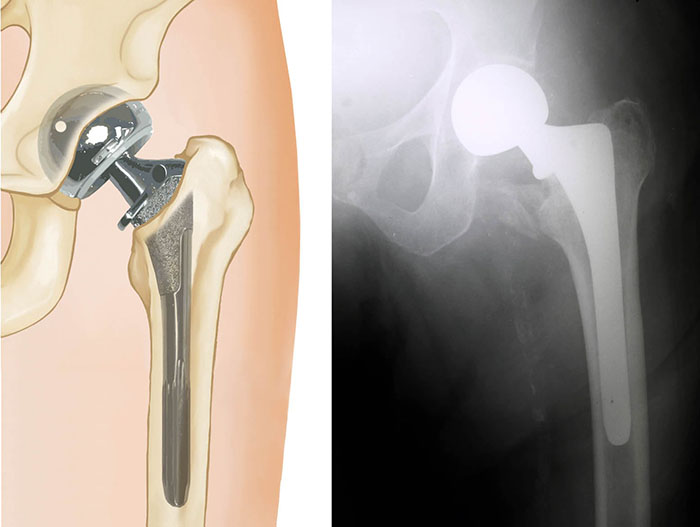

Fracture After Total Hip Replacement OrthoInfo AAOS How Long To Recover From Hip Fracture Surgery Surgery is usually the only treatment option for a hip fracture so that you can move again in comfort and begin your journey to recovery. Recovery from your broken hip is likely to take several months. First 24 hours following surgery: It can take 12 weeks for the bone to fully mend. We will continue to monitor. You will wake. How Long To Recover From Hip Fracture Surgery.